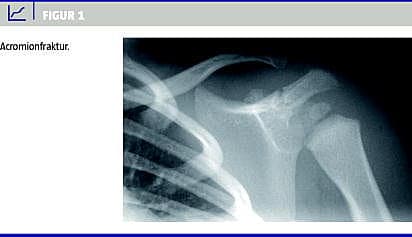

En 16 måneder gammel pige blev set på skadestuen på et regionssygehus, efter at hun to dage forinden havde haft et fald. Hun havde siden faldet ikke villet bruge sin venstre arm. På skadestuen blev der taget røntgenbilleder, der viste en acromionfraktur (Figur 1 ). Patienten blev sendt hjem, da frakturen skulle behandles konservativt. Da røntgenbillederne dagen efter blev gennemgået, blev der rejst mistanke om børnemishandling på grund af den noget usædvanlige fraktur. En søgning i EPJ blandt alle tilgængelige hospitaler gav resultat hos et centralsygehus, hvor patienten tre uger forinden var blevet undersøgt for columnafraktur. Patienten var angiveligt faldet to dage før iført et mariehønekostume, hvor hun var landet på en af dragtens vinger. Hun havde et stort hæmatom på ryggen, men der blev på daværende tidspunkt ikke fundet nogen frakturer, og hun blev sendt hjem. Ved denne undersøgelse fandt man normale forhold ved patientens skuldre og arme.

Summary The use of electronic medical records can contribute in diagnosing a case of battered child Ugeskr Læger 2013;175(5):284-285 Child abuse is a very serious offence and is often underdiagnosed. This case report shows how the use of electronic medical records from different hospitals aided in diagnosing a case of battered child in a 16-month-old girl with an unusual acromion fracture. This illustrates the need for thorough investigation of the records in cases where a fracture might not raise suspicion on its own.